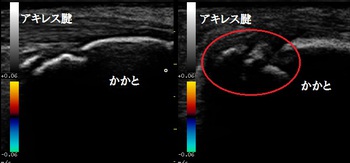

左踵(健側) 右踵 超音波長軸像 同部5週後

歩行時に踵を突いて歩くと激痛が起こります。超音波検査の結果、右踵の成長軟骨部に剥離した不正像が

認められました(上画像の丸の囲み)。

4週後、剥離した軟骨の状態を客観的に評価するために超音波検査の予定です。

5週後の超音波検査の結果、初診時に剥離していた軟骨が骨癒合してほとんど左右差が無くなりました。

痛みも消失し、運動制限なく部活動を行っております。